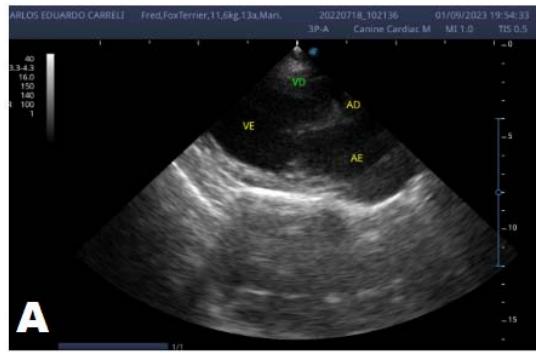

Keren Souza et al. Evolution of Degenerative Myxomatous Mitral Valve Disease in a Canine Fox Terrier: A Case Report